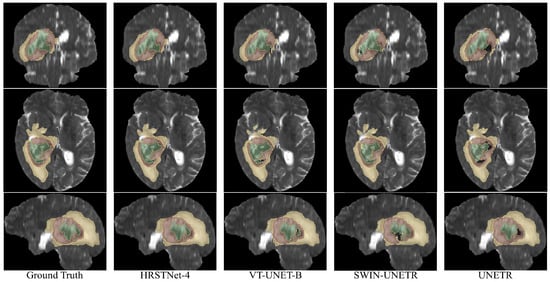

4.4. Experimental Results on BraTS 2021